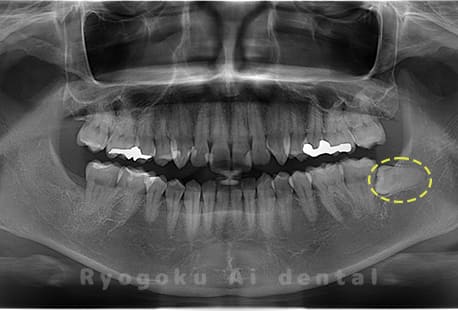

Case10

-

- 原因

- 下顎左の親知らず

- 治療内容

- 下顎左の親知らずを抜歯したケースです。

<リスク・副作用>

手術後は痛み、腫れ、痺れなどの副作用が生じる場合があります。